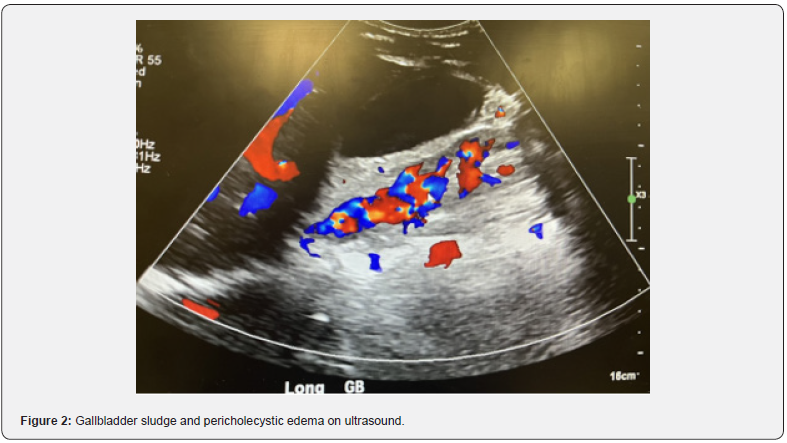

A 15-year-old male with no significant past medical history presented to the Emergency Department (ED) with right upper quadrant pain, nausea, vomiting, and decreased appetite evolving over a duration of 48 hours. On initial presentation, his work-up was remarkable for an elevated total bilirubin of 1.9, unremarkable CBC, and an x-ray showing subtle nodularity in the right colon indicative of possible colitis. Ultrasound was performed and the appendix was not visualized. He was discharged home from the ED with Toradol and Zofran for pain and nausea. He returned the next day with worsening right upper quadrant pain and fever (103 Fahrenheit). His nausea and vomiting had improved, but he continued to have a decrease in appetite. On examination, he was febrile, tachycardic, tachypneic, tender to palpation in the right upper quadrant area, had a negative Murphy’s sign and was jaundiced. Laboratory testing was repeated which showed an increasing total bilirubin from 1.9 to 3.7, mildly elevated ALT of 35, and elevated CRP of 8.5. CBC was unremarkable for leukocytosis, anemia or thrombocytosis. Computed Tomography (CT scan) of the abdomen and pelvis was performed which showed a normal appendix, massive stool burden in the cecum, possible sludge/ stones in the gallbladder with minimal pericholecystic fluid around the tip of the fundus and tip of the liver, with an inability to rule out cholecystitis and a horseshoe kidney with a dilated left renal pelvis (Figure 1). He was given 2 bisacodyl enemas which did improve his pain. A right upper quadrant ultrasound (RUQ) was performed showing gallbladder sludge and pericholecystic edema concerning for acalculous cholecystitis (Figure 2).